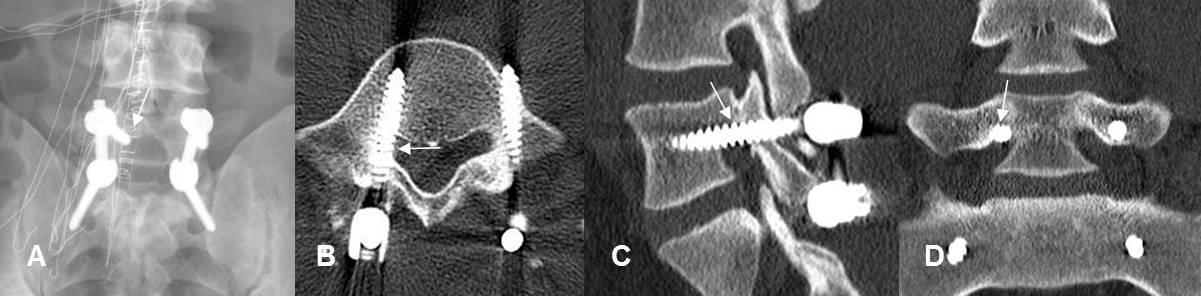

Fig 21. Mala posición de tornillos.

A: Rx AP. Tornillo superior derecho, con extremo medializado.

B: TAC axial. El tornillo rompe la cortical medial y ocupa el receso lateral.

C: TAC reconstrucción sagital y D: TAC reconstrucción coronal. El tornillo ocupa la parte superior del agujero de conjunción, lugar por donde sale la raíz nerviosa.